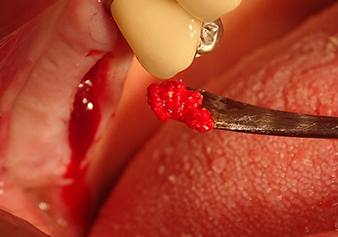

Following an intermediate check (Fig. 4) a further preparation step was performed (Fig. 5). Afterwards, the hydraulic Z35P instrument was used to lift the membrane to the desired position (Fig. 6 and 7). This was followed by further piezosurgical preparation of the implant bed, concluded with a rotary bur and shoulder milling cutter up to the implant diameter of 4.8 mm. Before the implant was inserted, the augmentation material (particle size approx. 0.8-1.6 mm) was introduced underneath the Schneiderian membrane (Fig. 8).

A periosteal elevator is used to place an augmentative mixture carefully into the region of the internal maxillary sinus ostium in the apical direction

Fig.8: A periosteal elevator is used to place an augmentative mixture carefully into the region of the internal maxillary sinus ostium in the apical direction.